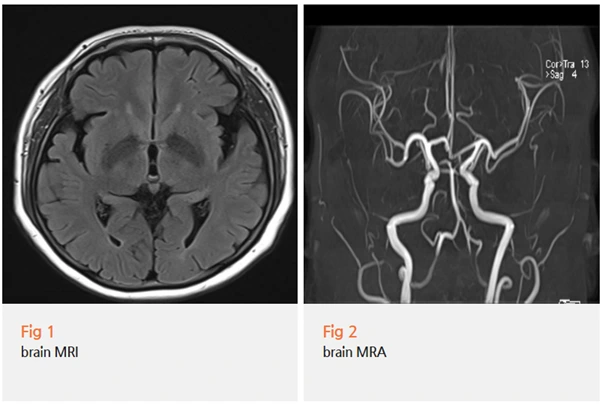

저는 이 환자분께 바로 당일 뇌 MRI와 MRA 검사를 권유드렸어요.

뇌경색 가능성을 먼저 배제해야 했기 때문입니다.

다행히 뇌 MRI·MRA 결과에서 뇌경색 소견은 없었습니다.

그제서야 구안와사, 즉 말초성 안면신경마비로 진단을 확정할 수 있었어요.